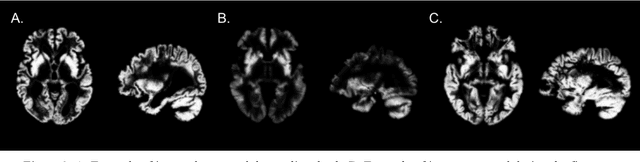

Abstract:The use of neural networks for diagnosis classification is becoming more and more prevalent in the medical imaging community. However, deep learning method outputs remain hard to explain. Another difficulty is to choose among the large number of techniques developed to analyze how networks learn, as all present different limitations. In this paper, we extended the framework of Fong and Vedaldi [IEEE International Conference on Computer Vision (ICCV), 2017] to visualize the training of convolutional neural networks (CNNs) on 3D quantitative neuroimaging data. Our application focuses on the detection of Alzheimer's disease with gray matter probability maps extracted from structural MRI. We first assessed the robustness of the visualization method by studying the coherence of the longitudinal patterns and regions identified by the network. We then studied the stability of the CNN training by computing visualization-based similarity indexes between different re-runs of the CNN. We demonstrated that the areas identified by the CNN were consistent with what is known of Alzheimer's disease and that the visualization approach extract coherent longitudinal patterns. We also showed that the CNN training is not stable and that the areas identified mainly depend on the initialization and the training process. This issue may exist in many other medical studies using deep learning methods on datasets in which the number of samples is too small and the data dimension is high. This means that it may not be possible to rely on deep learning to detect stable regions of interest in this field yet.